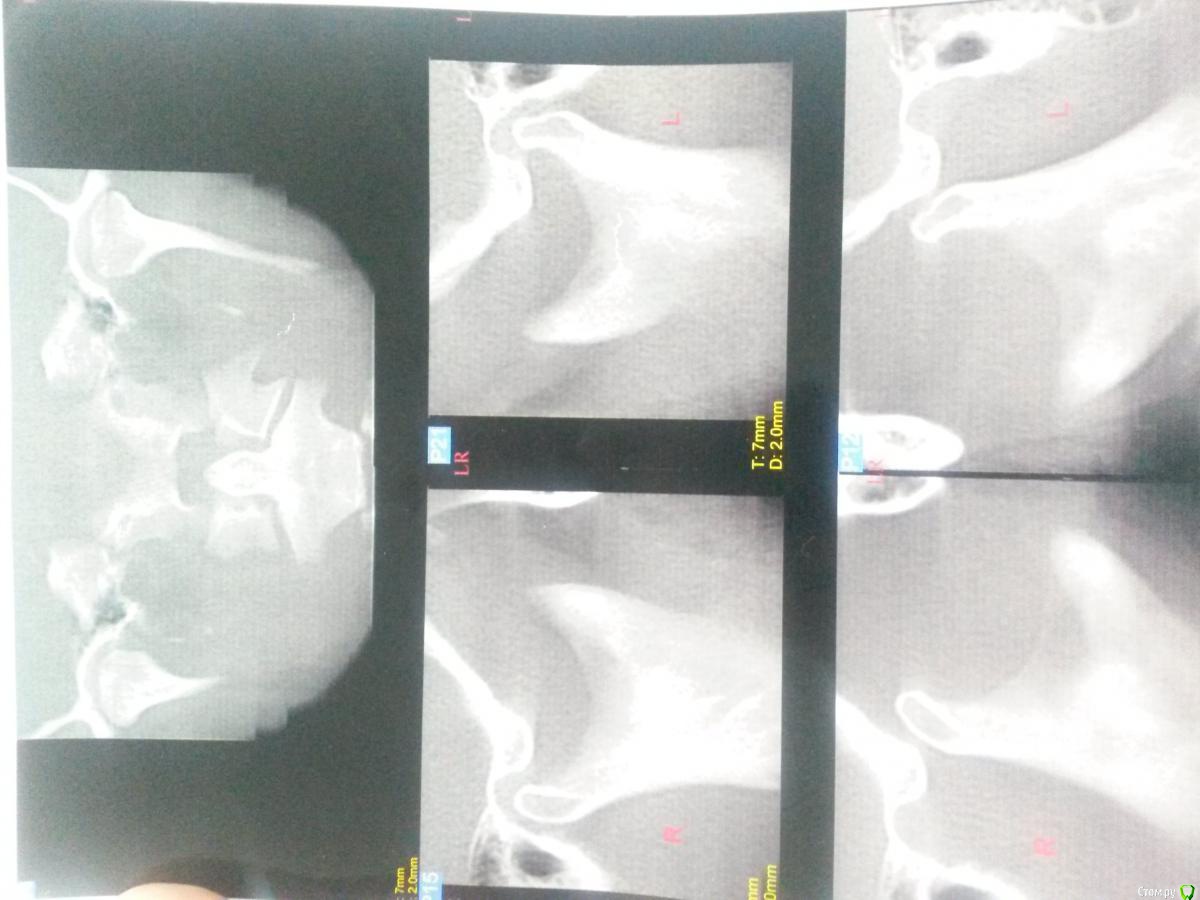

Nazim_NV86 Опубликовано 26 декабря, 2016 Поделиться Опубликовано 26 декабря, 2016 Пациент: 32 года. Девушка. Прикус ортогнатический. Вывихи происходят каждый раз во время приёма. Есть предложения доктора? Ссылка на комментарий

Maxfac Опубликовано 26 декабря, 2016 Поделиться Опубликовано 26 декабря, 2016 Какой-нибудь аппаратец: от Петросова до описанного Дж. Окесоном в виде ограничивающего эластика с фиксацией на кнопки. Хирургически можно, но это овертритмент. 1 Ссылка на комментарий